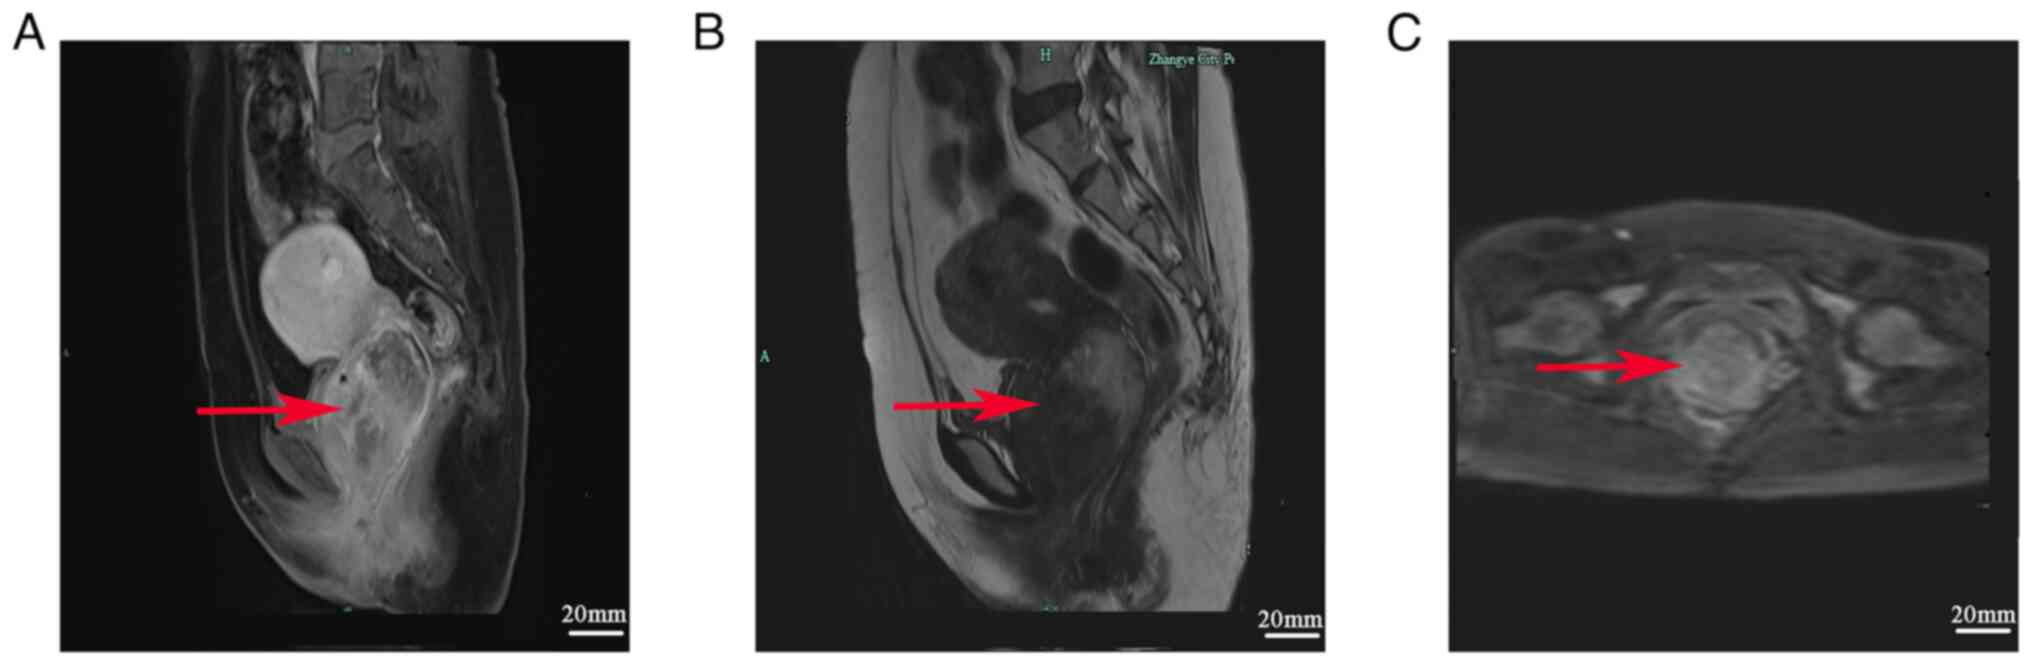

A 48-year-old female presented at the Emergency Department of a external hospital with a 2-day history of vaginal bleeding and a prolapsed hard vaginal mass, which was goose egg-sized. On examination, there was heavy vaginal bleeding with blood clots. Subsequently, the patient observed a hard mass that was the size of a goose egg in the vagina. The mass was able to be retracted when the patient was in the supine position, but it prolapsed when the patient stood or squatted. The patient also experienced urinary incontinence when coughing or sneezing. Pelvic magnetic resonance imaging (MRI) performed at another hospital indicated cervical cancer. As the exact diagnosis was unclear, the patient visited the gynecological clinic of Hexi University Affiliated Zhangye People's Hospital (Zhangye, China) in July 2021. Lower abdominal diffusion-weighted MRI performed on the first day after admission at Hexi University Affiliated Zhangye People's Hospital (Zhangye, China) revealed a soft tissue mass of ~65x46 mm at the anterior vaginal wall. The mass was isointense on T1-weighted imaging, iso-to hypointense on T2-weighted imaging and slightly hyperintense on diffusion-weighted imaging. Apparent diffusion coefficient imaging with a b-value of 800 revealed the tumor contour, and contrast-enhanced imaging revealed progressive and uneven enhancement. The solid mass was considered to be cervical cancer (Fig. 1).